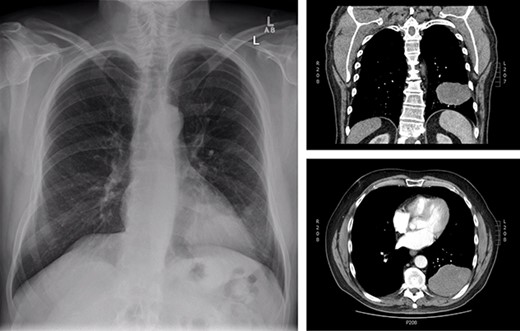

Initial presentation of solitary fibrous tumour in 2013 showing 9.3 × 6.1 cm left-sided pleural-based tumour.